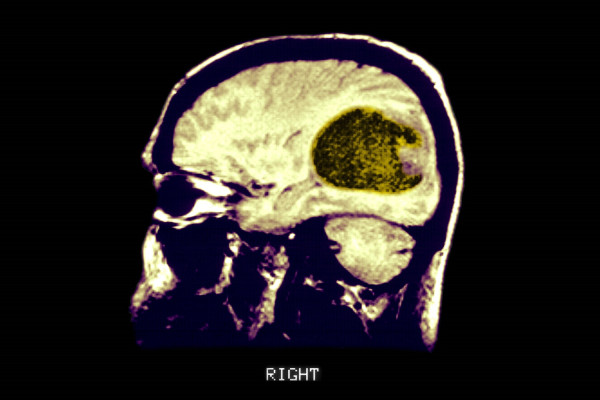

Σαρώσεις όπως η μαγνητική τομογραφία, σε συνδυασμό με τεστ γνωστικής απόδοσης, πραγματοποιήθηκαν στην αρχή της μελέτης και στη συνέχεια ξανά όταν οι συμμετέχοντες ήταν κατά μέσο όρο 70 ετών για να παρακολουθήσουν την πρόοδο και να εντοπίσουν σημάδια γνωστικής παρακμής.

Οι επιστήμονες διαπίστωσαν ότι οι εθελοντές που ακολουθούσαν μια «καλύτερη μεσήλικη διατροφή» είχαν βελτιωμένη συνδεσιμότητα μεταξύ του αριστερού ιππόκαμπου - του τμήματος του εγκεφάλου που παίζει βασικό ρόλο στην επεξεργασία και τη μνήμη - και του ινιακού λοβού, που βρίσκεται στο πίσω μέρος του εγκεφάλου και είναι κυρίως υπεύθυνος για την οπτική επεξεργασία.